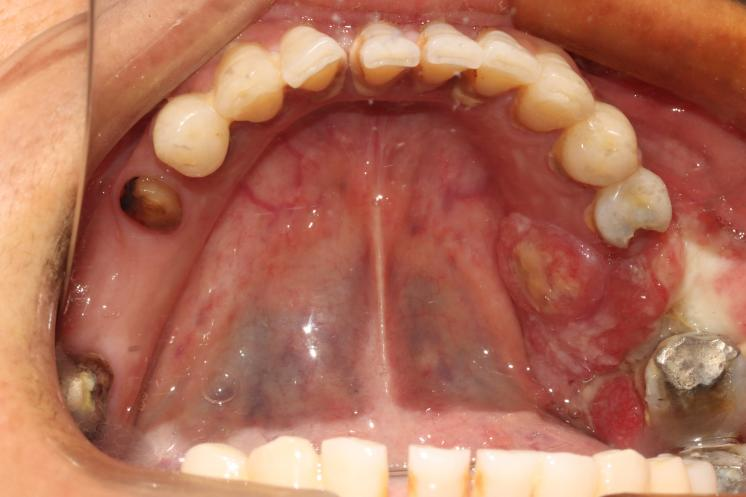

术前口内照

进一步检查发现,肿瘤已经突破了黏膜的边界,悄然侵入了下颌骨。“那……那怎么办?”老张的声音有些发抖。“别担心,我们还有办法。”医生的语气沉稳而坚定。